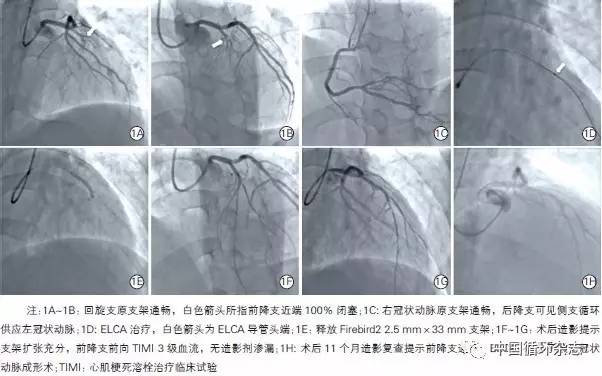

消融后应用顺应性球囊对病变血管段进行预扩张,球囊直径与参考血管直径比率为0.8~0.9:1.0。术中使用新一代药物洗脱支架。具体影像学变化可从39岁男性中可见一斑。

图1 39岁男性患者冠状动脉介入治疗影像学图